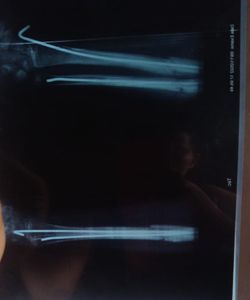

Será muito importante para a criança essa cirurgia pois não o osso não encana pois ela perdeu muita faixa óssea e necessita muito dessa cirurgia

Essa criança já passou por uma cirurgia e necessita de outra com platina de titânio